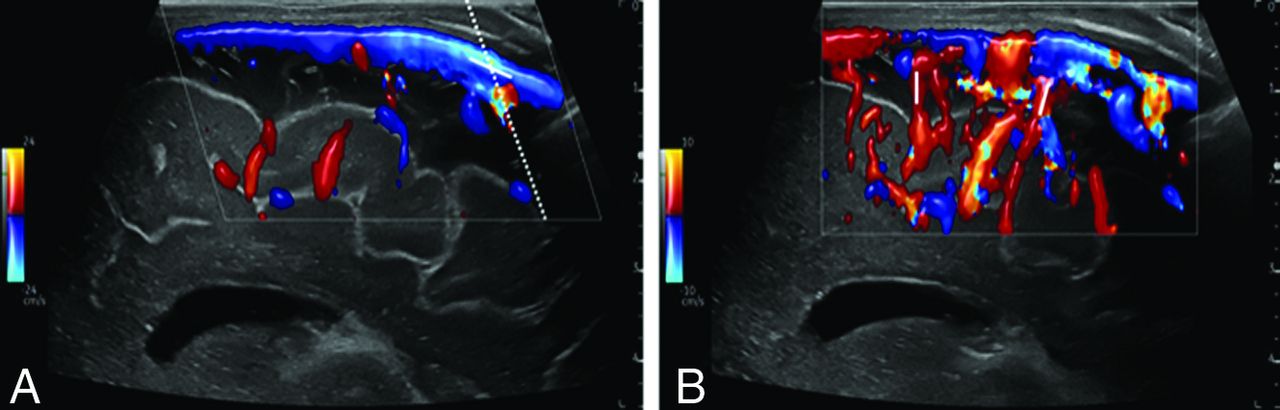

All US scans were obtained using 1 of 2 high-end US machines (LOGIQ S8/LOGIQ E10s R3; GE Healthcare) equipped with high-resolution linear transducers (ML5-15-D or ML4-20-D; GE Healthcare). Venous cerebral US Doppler flow measurements were documented only in calm, preferably sleeping, infants. US Doppler FPs in the superior sagittal sinus (SSS) were recorded using a median sagittal section (Fig 1). First, the SSS was visualized in a longitudinal section at a low penetration depth in B-mode and color-coded Doppler US with flow displayed over the entire vessel section. Next, an angle-corrected pulsed Doppler time-frequency analysis of intravascular flow in a far posterior vessel segment before the junction of any VGAM drainage veins was performed. The sample volume was adapted until the entire width of the vessel was captured. Visual and acoustic reassurance of an optimal time-frequency Doppler signal ensured that the sample volume passed through the center of the vessel. Doppler FPs in the cortical veins were measured with the same transducer, following the same optimization steps (Fig 2B). The FPs were only evaluated for this study if the Doppler flow curves had sufficient image quality, ie, correct positioning of the sample volume, correct wall filter, correct pulse repetition frequency, and sufficient Doppler signal for at least 5 seconds.

Doppler imaging protocol of the SSS and cortical veins in a median sagittal section. A, SSS in median sagittal section in color-coded Doppler US with tilted Doppler beam (dotted line) and corresponding angular correction (white line). B, Cortical arteries and veins in sagittal section in color-coded Doppler US show possible measurement points (white lines).